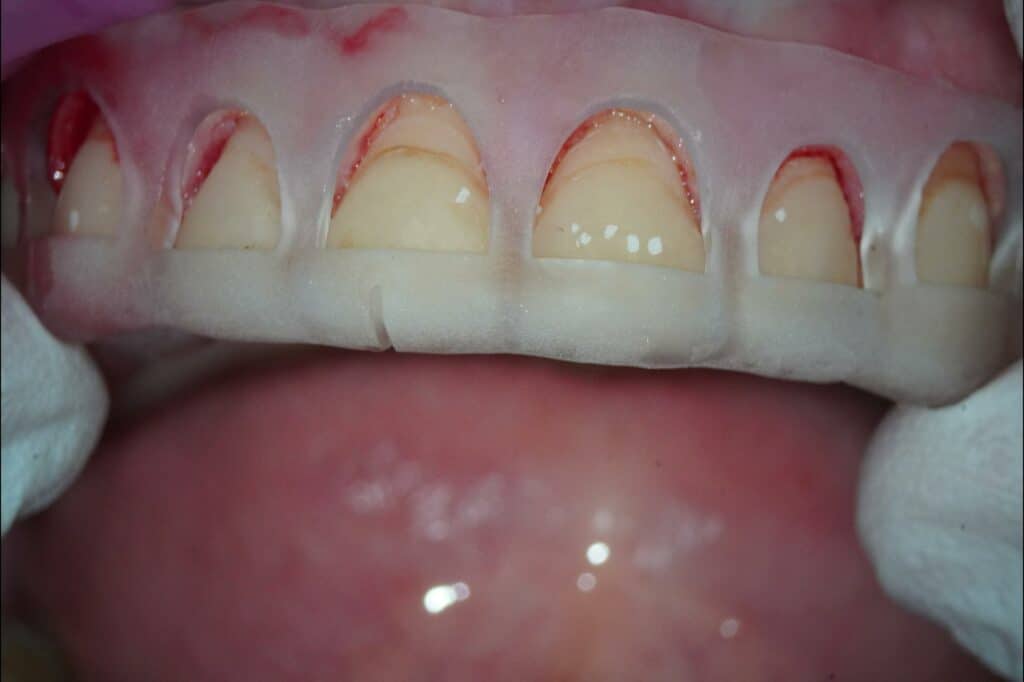

Mit der CAD-Software Exocad wurde die anschließend gedruckte Zahnfleisch-Prä-parationshilfe designt (Abb. 6 und 7). Der Behandler nahm die geführte laserge-stütze Gingivektomie vor (Abb. 8 bis 10).

Anschließend wurden die Zähne 15 bis 25 präpariert und die Präparationen mit einem Intraoralscanner erfasst. Auf der Grundlage der STL-Daten der digitalen Abformung wurden im Dentallabor des Autors die Kronen aus PMMA mit der De-sign-Software 3Shape geplant (Abb. 11 bis 13). Dabei erstellte die Software aus dem 2-D-animierten Bild einen 3-D-Out-put (Abb. 11). Diese STL-Datei wurde dann händisch in die Konstruktionssoft-ware eingesetzt und wie zuvor mit der